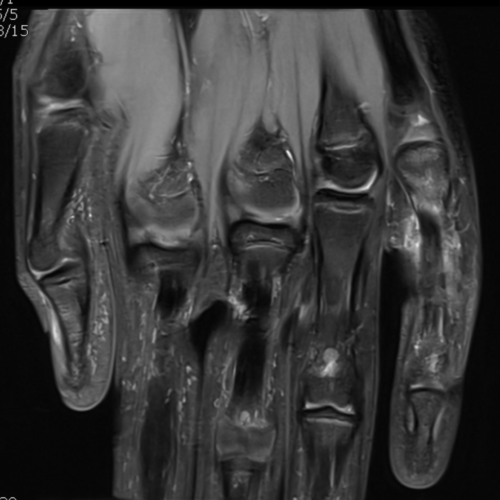

Cet examen est réalisé pour analyser les structures anatomiques des doigts en cas de douleur, traumatisme, tuméfaction (boule) sur un doigt ou la main, de coupure, de déformation d’un doigt.

Cette examen permets de diagnostiquer:

- Les tendinites

- Les ruptures de poulies

- Les rhumatismes

- Les ruptures de plaque palmaire

- Les ruptures tendineuses

- les arthrites

- la maladie de Dupuytren

- les doigts à ressaut

- l’arthrose digitale

- le mallet finger

- le jersey finger

- le kyste synovial